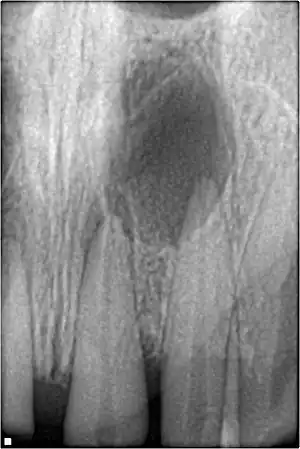

![]() | |

| Xray showing peri-radicular radiolucency and bone loss caused by an odontogenic infection under the roots of two anterior teeth | |